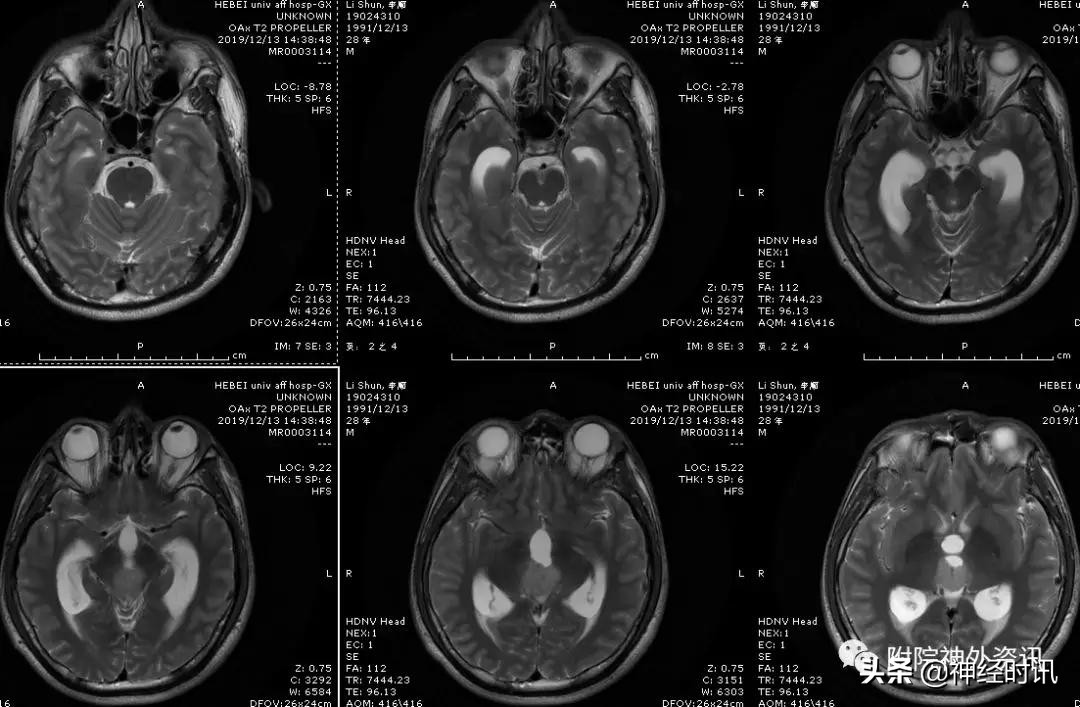

男性,28岁,主因复视20余天入院,查体双瞳孔不等大,直径左=3. 5mm,右=3.0 mm,对光反射迟钝,双眼上视困难,左眼眼位异常,向内下斜视。